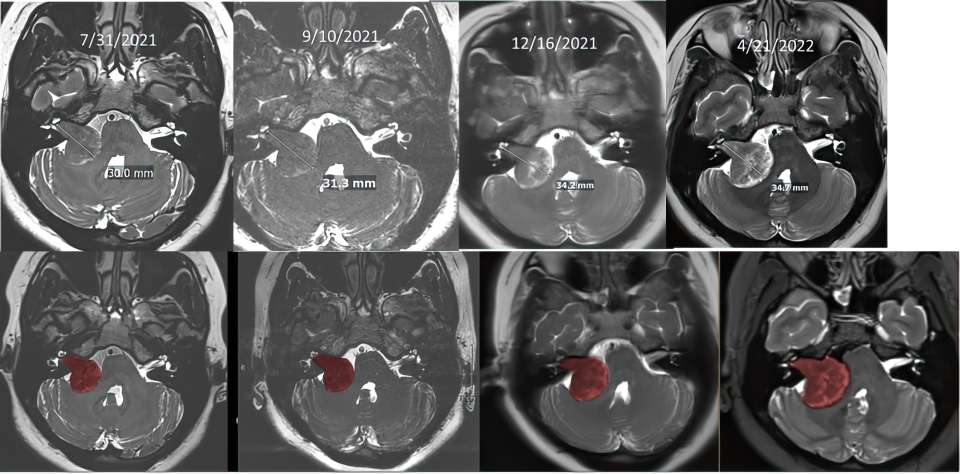

To monitor the growth of the tumor and the development of hydrocephalus, Sun underwent several scans throughout her pregnancy.

“We couldn’t use CT scans because they involve radiation, which can be harmful to the fetus,” explained Dr. Everson. “While an MRI is safe, the typical scan takes about an hour lying flat, which is difficult for patients to tolerate in late pregnancy. So, we worked closely with radiologist Dr. Noriko Salamon to devise a specific, shortened MRI protocol that gave us all the detail we needed to monitor tumor growth.”

The team observed subtle signs of tumor growth during Sun’s second and third trimesters and remained vigilant, closely monitoring her condition with frequent brain scans. This involved close collaboration with radiology, ENT specialists, and her OBGYN team, which included Carla Janzen, MD, PhD, an expert in maternal-fetal medicine and high-risk pregnancies, and obstetrician-gynecologist Brittany Davis, MD.

After the extensive surgery, Dr. Everson and his team were able to remove the now golf ball-sized tumor without any damage to the facial nerve. In the years since, the team has continued to monitor Sun to ensure everything stayed stable.